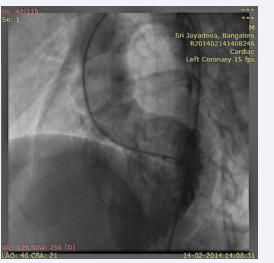

and a small ostium secundum atrial septal defect (left to right shunt). Furthermore, there was thickening of the interventricular septum that appeared as a pouch. The patient underwent cardiac catheterization to define the anatomy and determine the complexity because the VSD was not confirmed. The QP:Qs was 1:1. The left ventriculography revealed a normal contractile ventricle connected to the left sided aorta. There was no evidence of VSD. However, there was opacification of a small pouch just medial to the septum. There was no opacification of the pulmonary artery (Figure 5; video7)

Figure 5: LV angiogram in LAO view showing opacification of left sided aorta and a pouch medial to septum and no evidence of VSD.

Video 7: LV angiogram in LAO view showing opacification of the left sided aorta and a pouch medial to septum.